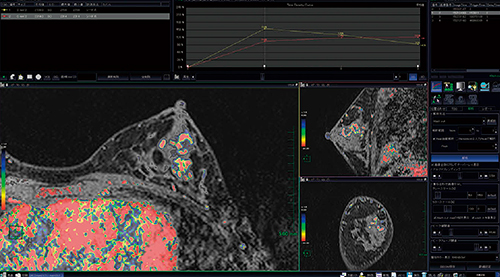

乳がんに対するMR画像診断では,造影によって複数時相を撮像するダイナミック造影検査が一般的に施行されています。乳がんは早期濃染とピーク信号値に対して15%程度の造影剤洗い出し(Wash out)が見られるという特徴を有するため,読影医は関心領域(ROI)でのタイムインテンシティカーブ(TIC)を描画することによって腫瘍の性状評価を行っていました。今回開発したWash out mapは,複数時相データのすべてのピクセルでTIC計算を行い,ピークの信号値,最終フェイズの信号値からWash outの強度に合わせて画像をカラーマッピングする機能です(図1)。これによって,腫瘍性状の局在を把握することが容易になります。

図1 Wash out map

洗い出し強度から腫瘍の性状を評価可能